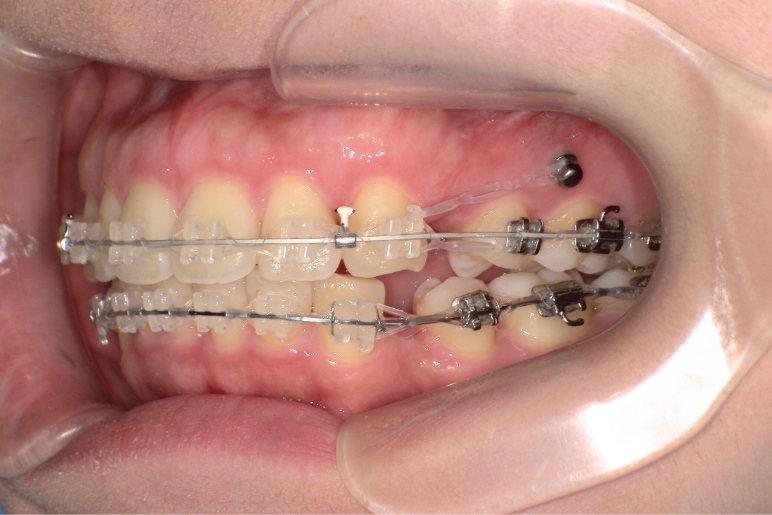

装置名 ワイヤー矯正、矯正用アンカースクリュー2本

抜歯部位 上顎右側第一小臼歯、上顎左側第二小臼歯、下顎左右第一小臼歯

治療期間 2年

費用 ¥910,000(税込¥1,001,000)

リスク・副作用 痛み、歯根吸収、歯肉退縮、虫歯、後戻り

治療のポイント 上顎前突でガミースマイルの場合、抜歯して、第二小臼歯と第一大臼歯の間にアンカースクリューを使用し、後上方に圧下しながら歯を下げることで、上唇が閉じやすくなるので歯茎が見えづらくなります。